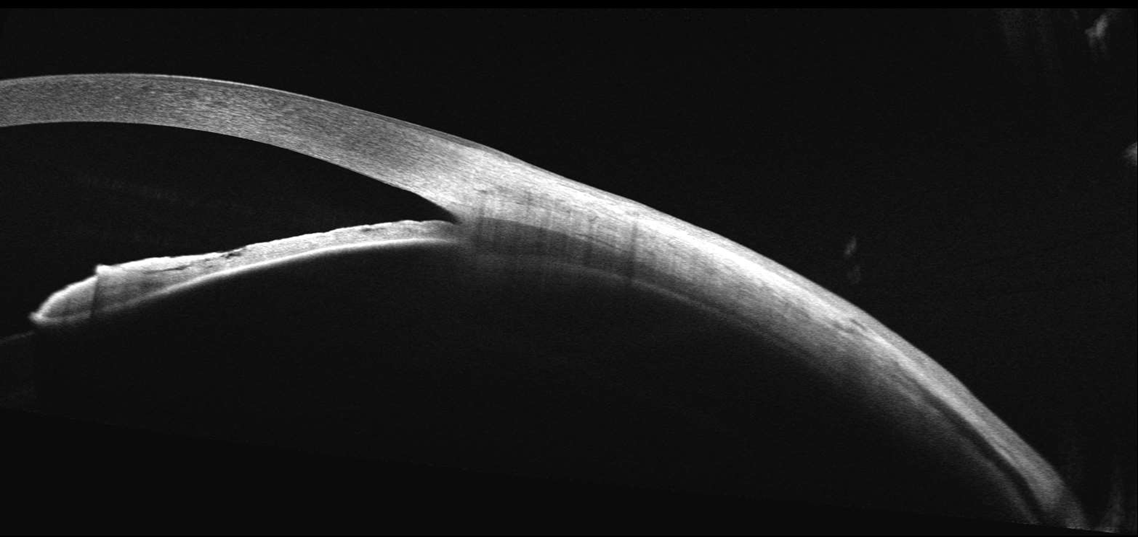

- Analyse Chambre Antérieure.

- Biométrie OCT : B-OCT® est une méthode innovante d'utilisation du dispositif OCT postérieur pour mesurer la structure oculaire le long de l'axe de l'œil. Un calculateur IOL est également disponible.